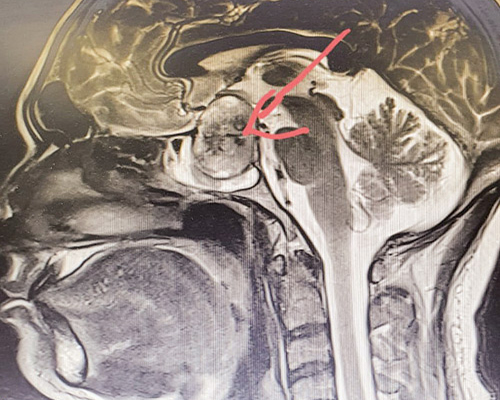

تمكّن فريق طبي في قسم جراحة المخ والأعصاب بمستشفى الملك خالد بتبوك من إعادة النظر تدريجياً لمريض بعد فقدان مفاجئ للبصر، حيث تبيّن بعد إجراء الفحوصات الإشعاعية والمخبرية وجود نزيف حاد وورم كبير بالغدة النخامية بالمخ وعلى الفور تم إدخاله غرفة العمليات وإجراء جراحة طارئة لاستئصال الورم النازف؛ وذلك باستخدام المنظار الجراحي عن طريق الأنف، حيث استغرقت العملية ما يقارب ثلاث ساعات، وتم بحمد الله من خلالها استئصال الورم بنجاح وبدون أي مضاعفات.

وقد بدأ المريض بالاستجابة تدريجياً للنظر مرة أخرى وغادر المستشفى بعد أن تلقى الرعاية الطبية اللازمة.